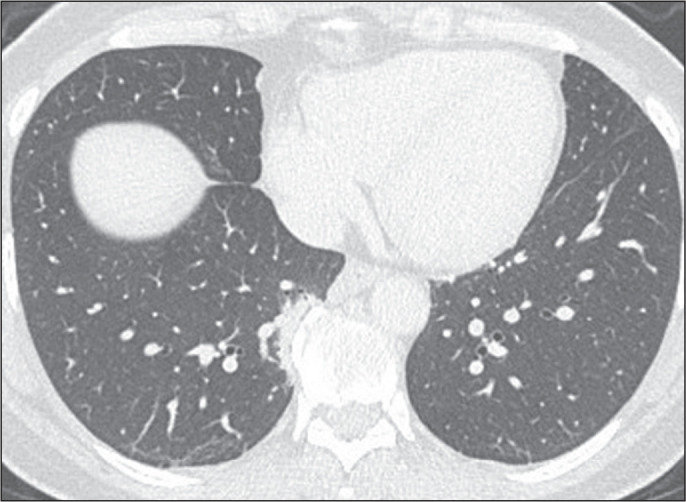

Objective: To conduct a survey on the use of the term "interstitial lung abnormalities" in radiology reports in Brazil, propose an appropriate Portuguese-language translation for the term, and provide a brief review of the literature on the topic.

Results: A total of 163 responses were received, from all regions of Brazil. Although the vast majority (88%) of the respondents stated that they were familiar with the term "interstitial lung abnormalities", there was considerable variation regarding the equivalent term they used in Portuguese.

Conclusion: We suggest that the term "anormalidades pulmonares intersticiais" be used in order to standardize radiology reports and disseminate knowledge of these findings in Brazil.